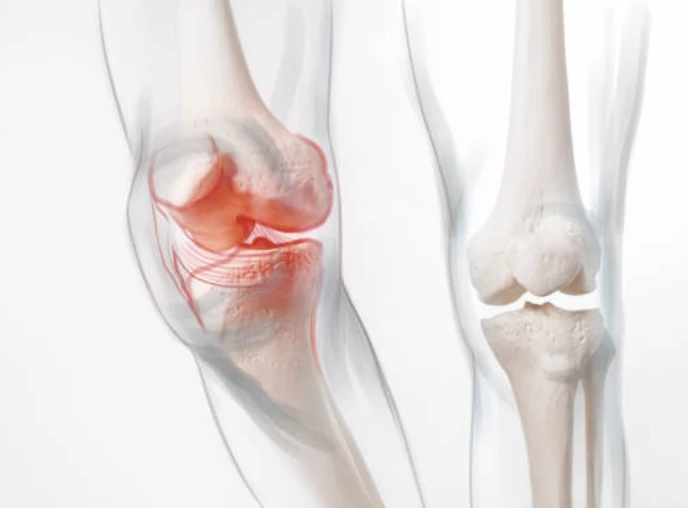

무릎의 구조

무릎이 어떤 부분으로 구성되어있는지 간략하게 살펴보겠습니다. 무릎은 들어 올리기, 무릎 꿇기 등의 일상적인 활동과 걷기 및 달리기, 에어로빅과 같은 고강도 활동으로 인해 많은 스트레스를 받는 취약한 관절입니다. 무릎 통증 원인은 이유가 다양할 수 있습니다.

각 뼈의 끝은 충격을 흡수하기 위해 연골층이 덮여있습니다. 기본적으로 무릎은 근육과 인대 그리고 힘줄에 의해 결합된 2개의 다리뼈입니다.

힘줄은 근육과 뼈를 연결하는 질긴 조직입니다. 인대는 뼈와 뼈를 연결하는 조직의 탄성 밴드와 같은 역할을 합니다. 무릎의 일부 인대는 관절의 안정성과 보호를 제공하지만, 다른 인대는 정강이 뼈의 앞뒤 움직임을 제한합니다.

무릎 통증 원인

- 염좌 또는 긴장된 무릎 인대와 근육은 일반적으로 무릎에 대한 타격이나 무릎의 갑작스러운 비틀림으로 인해 발생합니다. 해당 증상으로는 통증, 붓기, 움직이지 못함 등이 있습니다.

- 무릎 연골 손상은 무릎 외상으로 인해 반월판(충격 흡수제 역할)이 찢어지는 것입니다. 연골 파열은 종종 염좌와 함께 발생할 수 있는데, 치료방법에는 추가 부상으로 부터 무릎을 보호해 줄 무릎보호대를 착용하는 것이 포함됩니다.

- 관절염은 무릎에 영향을 미치는 가장 흔한 질병입니다. 골관절염은 관절의 연골이 서서히 마모되는 퇴행성 과정입니다. 이는 종종 중년 및 노인에게 쉽게 영향을 끼칩니다. 관절염은 반복적인 부상이나 과체중으로 인한 관절 스트레스 발생할 수 있습니다.